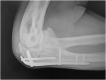

Upper extremity function is highly dependent on elbow motion in order to adequately position the hand in space. Loss of this motion due to stiffness following trauma can cause patients substantial disability, leading to difficulties with performing activities of daily living. Post-traumatic elbow stiffness is challenging to treat, and therefore prevention is of paramount importance. Key measures that can be used to prevent elbow stiffness are early surgical intervention for fracture or joint instability, as well as active mobilisation, which helps to prevent oedema and an increase in viscosity of inflammatory exudates. Other options include splinting and continuous passive mobilisation. Once non-operative methods of addressing post-traumatic stiffness have been exhausted, arthrolysis of the stiff elbow can be performed via open or arthroscopic means depending on the type of pathology involved (intrinsic or extrinsic contracture) and experience of the surgeon with elbow arthroscopy. The particular open approach used depends on several factors, which include the formation and location of any heterotopic ossification present. Improvements in range of motion can be expected with both open and arthroscopic techniques, which can be effective and rewarding for patients. Post-operative rehabilitation, particularly early active mobilisation, should be considered essential in order to optimise patient outcomes following surgery. This review aims to explore elbow stiffness following traumatic aetiology, assessing its pathogenesis and prevention, as well as reviewing surgical treatment options and post-operative rehabilitation.